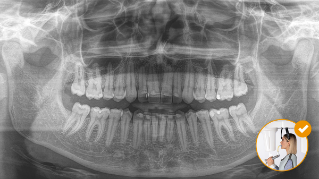

Il risultato: scansioni precise grazie al morso occlusale

Posizionamento corretto del paziente con il morso occlusale - inclinazione ideale garantita per le immagini panoramiche